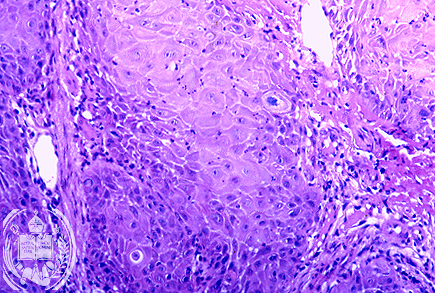

Fig. 47-B2: Carcinoma

Histológicamente se encontró un carcinoma espinocelular.